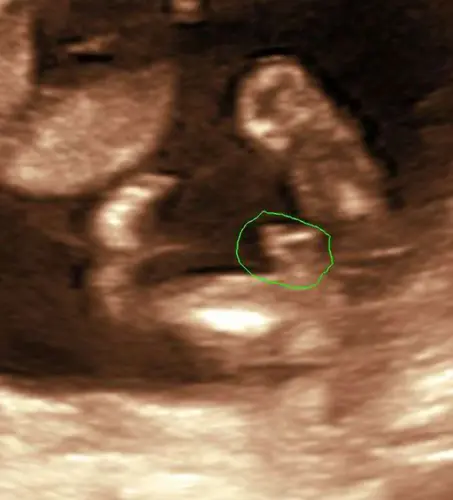

Echoscopist zei jongen met 15 weken? Dan mag je daar gerust van uitgaan. Bedenk ook dat een echoscopist live heeft gekeken en daarbij ook nog gediplomeerd en ervaren is. Wij zijn dat hier niet.

Klopt! Maar ik ken mensen waar het dus ook een meisje bleek te zijn terwijl de professional zei jongen met 15 weken. Dus was toch benieuwd of er mensen waren die wellicht ervaring hebben met een zelfde soort echo beeld.